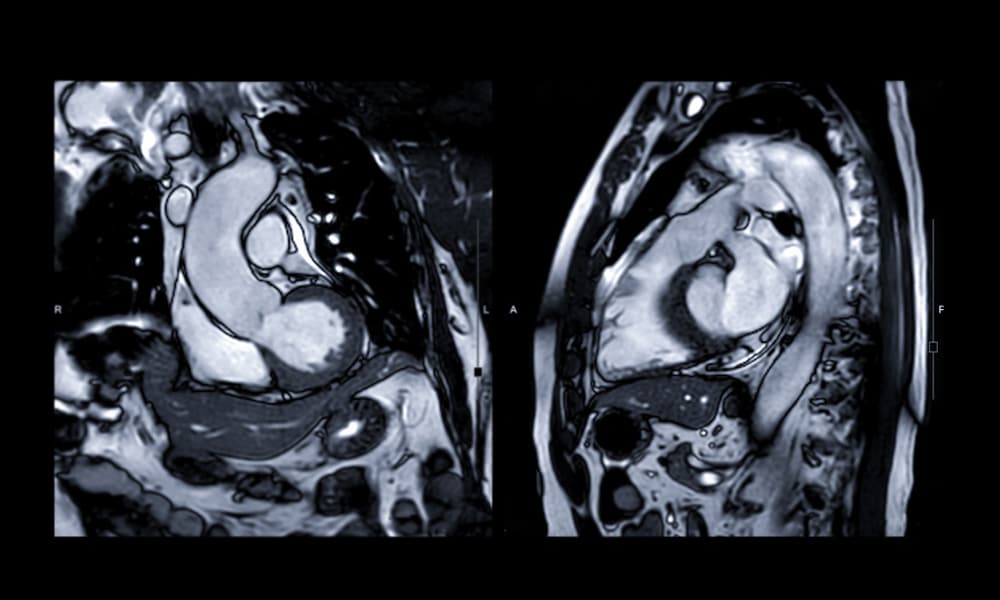

IRM 1.5 T Dernière Génération

Comment se déroule une IRM ?

L’imagerie par résonance magnétique (ou IRM) est un examen basé sur l’utilisation de champs électromagnétiques. Il donne des images du corps en deux ou trois dimensions. Pour bien vous y préparer et faciliter son déroulement, voici quelques conseils.

QU’EST-CE QU’UNE IRM ?

Une IRM (imagerie par résonance magnétique) est un examen de radiologie qui utilise un appareil émettant des ondes électromagnétiques, grâce à un gros aimant. Soumis à ces ondes, les atomes d’hydrogène composant les tissus de l’organisme se mettent à vibrer. Ils émettent alors des signaux, captés par une caméra spécifique et retranscrits en images sur un écran d’ordinateur.

L’IRM est un examen indolore, permettant d’obtenir des images de l’intérieur du corps humain, en 2 ou 3 dimensions. On le prescrit notamment pour visualiser les « tissus mous » (cerveau, moelle épinière, viscères, muscles, tendons, etc.)

Cette technologie, qui n’utilise pas les rayons X, est sans risque d’irradiation pour le patient.

Imagerie Cardio-vasculaire